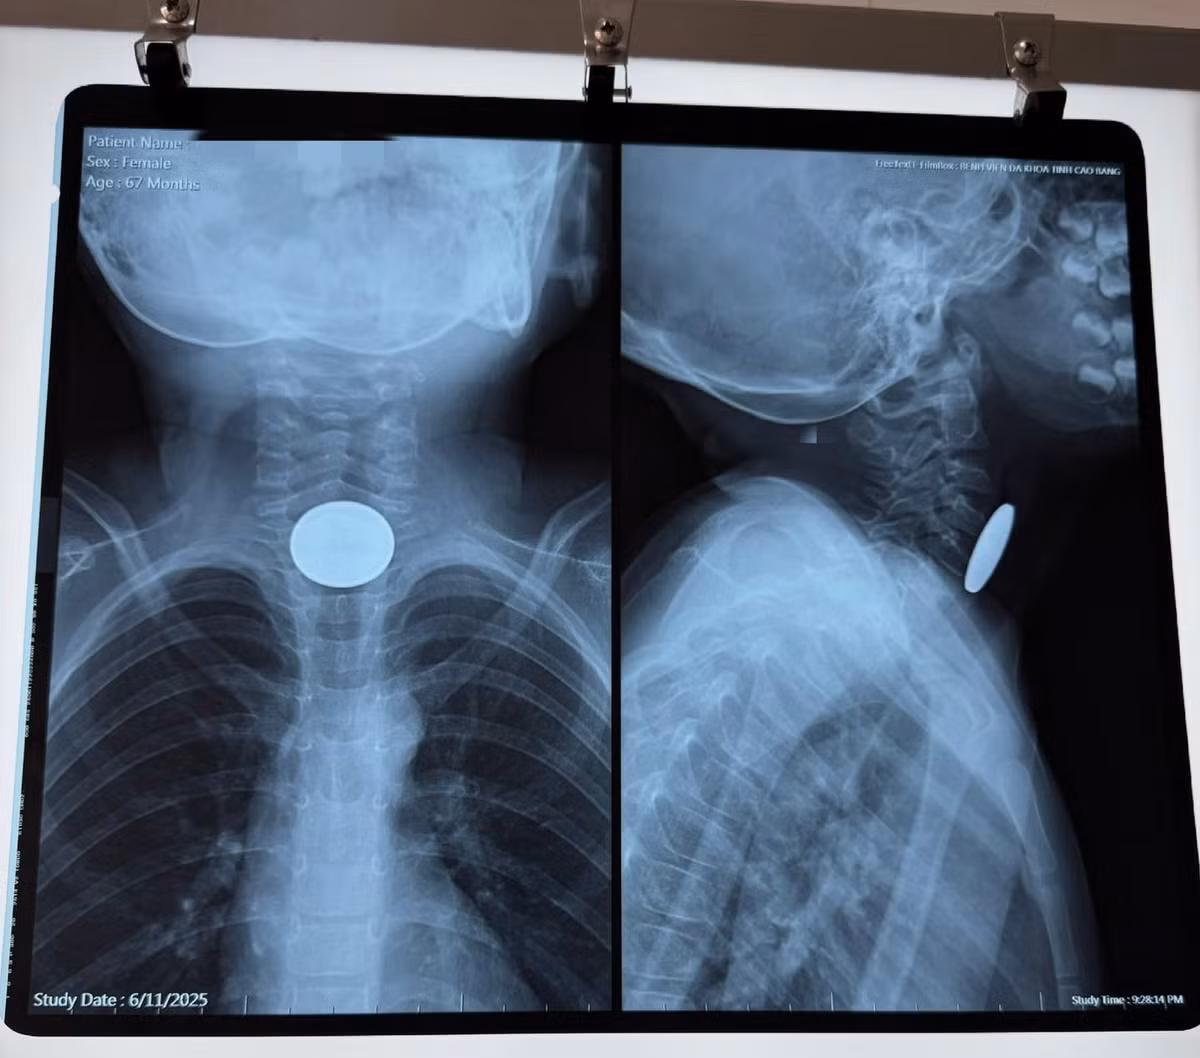

Đồng xu 2,5 cm mắc kẹt trong thực quản bé gái hơn 5 tuổi

Phụ huynh cần đặc biệt lưu ý không để trẻ chơi với các vật nhỏ, dễ nuốt như đồng xu, pin cúc áo, đồ lắp ráp nhỏ…

Ngày 11/6, Bệnh viện Đa khoa tỉnh Cao Bằng vừa tiếp nhận và xử trí thành công một trường hợp trẻ nhỏ nuốt dị vật nguy hiểm. Bệnh nhi là bé gái hơn 5 tuổi, trú tại thành phố Cao Bằng, được người nhà đưa đến bệnh viện trong tình trạng không nuốt được, buồn nôn nhưng không nôn được, khó thở sau khi chơi một mình tại nhà.

nuot-dong-cu.jpg

Hình ảnh dị vật đồng xu trên phim chụp - Ảnh BVCC